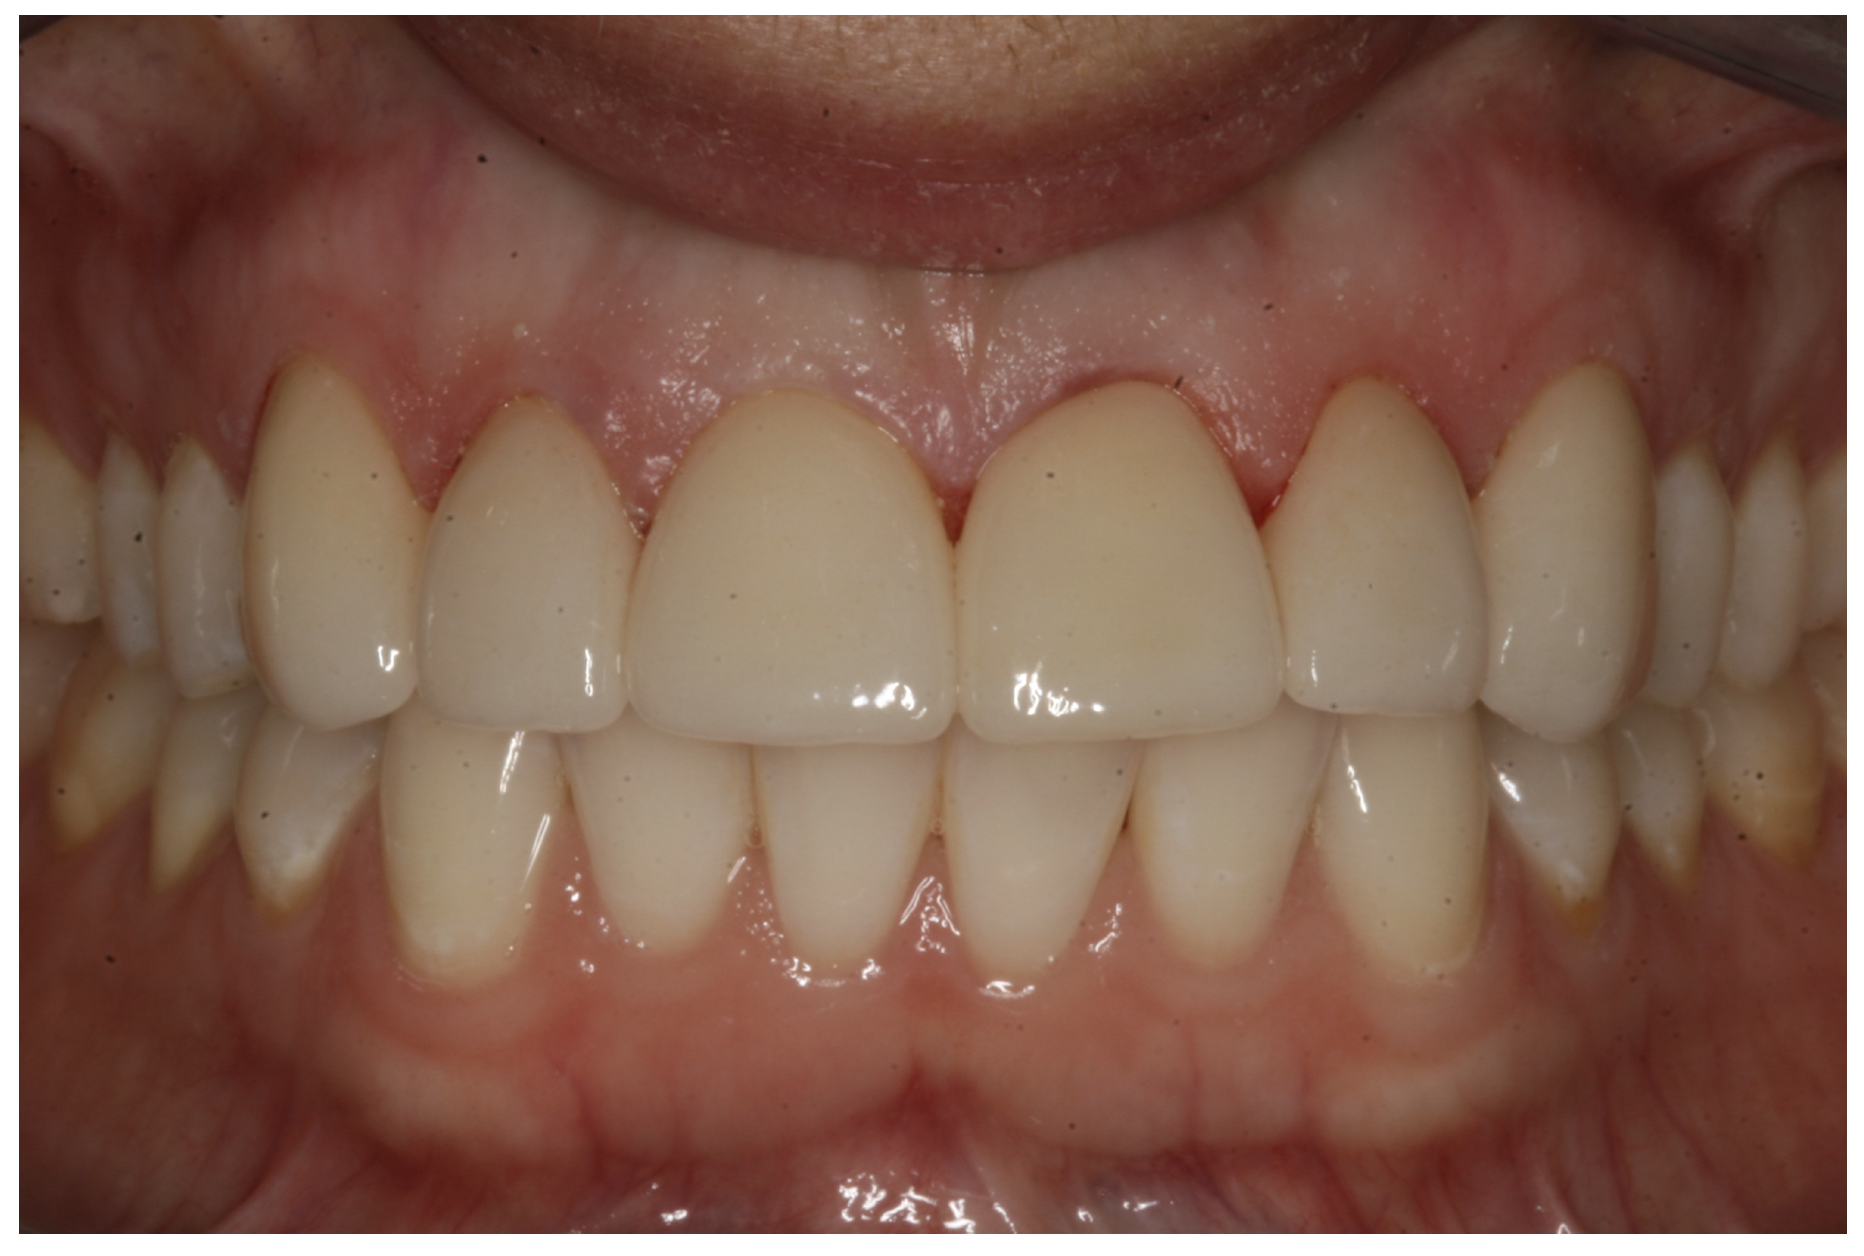

In another case, the patient presented with very thick, bulky, over-contoured veneers done on teeth Nos. 7 through 10 when she was a teenager. There also was some recession and staining at the margins (Figure 12). The clinician decided to restore teeth Nos. 6 through 11. A preparation design was required with provisionals removed. As tooth structure could not be regrown, the practitioner made the best of the situation. There was good gum health, which is important for isolation and marginal seal. The clinician cemented with a universal, doing six units at one time. Minimal cleanup was required. At a 1-month follow-up visit, although tissue still was settling in, the contours were natural. After a year (Figure 13), the gum filled in nicely and was in excellent health, and there was good color stability and seamless marginal integrity.